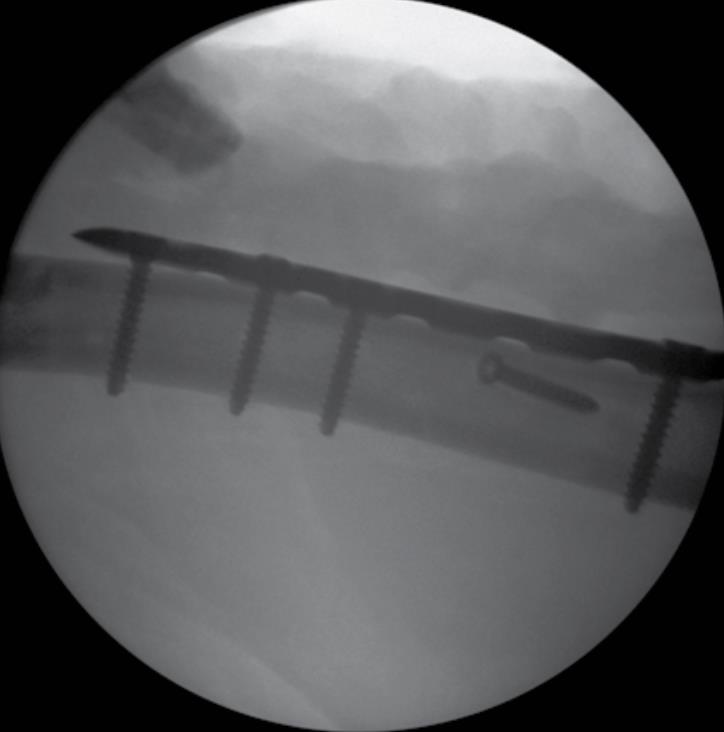

• Final Confirmation

• Confirm proper reduction, alignment and screw length with fluoroscopy.